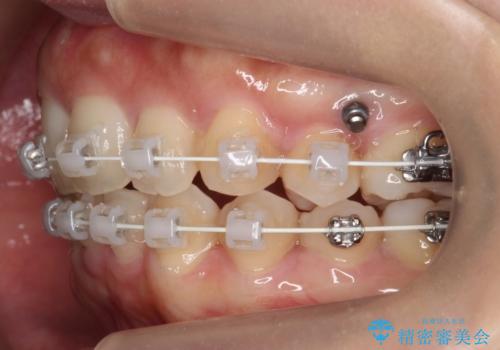

- 矯正装置

- ワイヤー矯正

- 2年4ヶ月

- 治療回数

- 10-30回